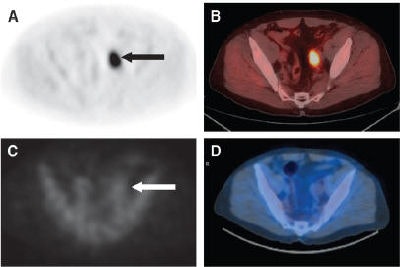

| Axial PET (A) and fused (B) anti-F-18-FACBC images in 67-year-old male patient with intense activity in left external iliac nodes (black arrow in A). SPECT/CT indium-111 capromab-pendetide axial (C) and CT fused (D) images demonstrate no significant activity in this region (white arrow in C). Copyright © by the Society of Nuclear Medicine Inc. Reprinted with permission from “Initial Experience With the Radiotracer Anti-1-Amino-3-18F-Fluorocyclobutane-1-Carboxylic Acid With PET/CT in Prostate Carcinoma,” Schuster DM, John R, Votaw JR, et al, urology department; and F. DuBois Bowman biostatistics department, Emory University in Atlanta, January 2007, Journal of Nuclear Medicine. |

Lymph node status with anti-F-18-FACBC showed seven of the nine patients in concordance with clinical follow-up, with the other two patients noted as indeterminate on imaging. In the six-patient group with suspected recurrence of prostate cancer, the anti-F-18-FACBC scan detected neoplasia in four patients with proven recurrence.